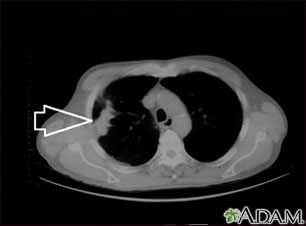

A chest CT (computed tomography) scan is an imaging method that uses x-rays to create cross-sectional pictures of the chest and upper abdomen.

A chest CT may show many disorders of the heart, lungs, mediastinum, or chest area, including:

- A tear in the wall, an abnormal widening or ballooning, or narrowing of the aorta, the major artery carrying blood out of the heart

- Other abnormal changes of the major blood vessels in the lungs or chest such as blood clots (pulmonary embolism)